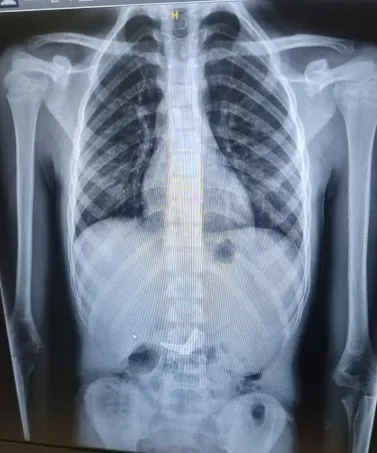

כשי' נמצא בהרדמה מלאה בחדר הניתוח, בוצע צילום נוסף כדי לבחון את מיקום ומצב המספרים. בצילום התברר כי המספריים נסגרו מעצמם, עברו את הקיבה והגיעו לעומק המעי הדק. "הייתה סכנה שהמספריים הפתוחים יגרמו לפציעה לושט או לקיבה ורצינו לבצע בדיקה על מנת לאתר ולשלוף אותם", אומרת ד"ר אסתר אורלינסקי-מאייר, מומחית בגסטרואנטרולוגיה ילדים בשערי צדק. "באורח פלא ומסיבה לא ברורה, ראינו שהמספריים נסגרו מעצמם, כך שהסכנה לפציעה בדרכי העיכול פחתה".

לאור כך, בהתייעצות של כלל הצוותים הרלוונטיים, הוחלט שלא לנתח את י' והוא הועבר להמשך השגחה צמודה במחלקת כירורגיה ילדים. "בליעה של מספריים על ידי ילדים, בטח בגיל בוגר יותר, היא אירוע חריג ביותר", אומר ד"ר אורי בליך, מומחה בכירורגיה ילדים בשערי צדק. "במכלול השיקולים ובהם, מצבו הטוב של י' וסגירת המספריים שהפחיתה את הסיכון לפציעה, החלטנו שלא לבצע התערבות כירורגית, שכן להליך זה עלול להיות סיבוכים שונים, בדומה לניתוחים כירורגיים אחרים".